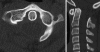

Background: The embryology of the bony craniovertebral junction (CVJ) is reviewed with the purpose of explaining the genesis and unusual configurations of the numerous congenital malformations in this region. Functionally, the bony CVJ can be divided into a central pillar consisting of the basiocciput and dental pivot and a two-tiered ring revolving round the central pivot, comprising the foramen magnum rim and occipital condyles above and the atlantal ring below. Embryologically, the central pillar and the surrounding rings descend from different primordia, and accordingly, developmental anomalies at the CVJ can also be segregated into those affecting the central pillar and those affecting the surrounding rings, respectively.

Discussion: A logical classification of this seemingly unwieldy group of malformations is thus possible based on their ontogenetic lineage, morbid anatomy, and clinical relevance. Representative examples of the main constituents of this classification scheme are given, and their surgical treatments are selectively discussed.